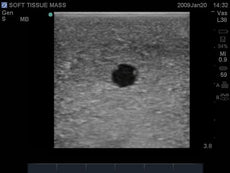

Replacement tissue insert for the Thoracentesis and Thoracostomy Ultrasound Training Model (BPTT1000-1).Choose from three options: